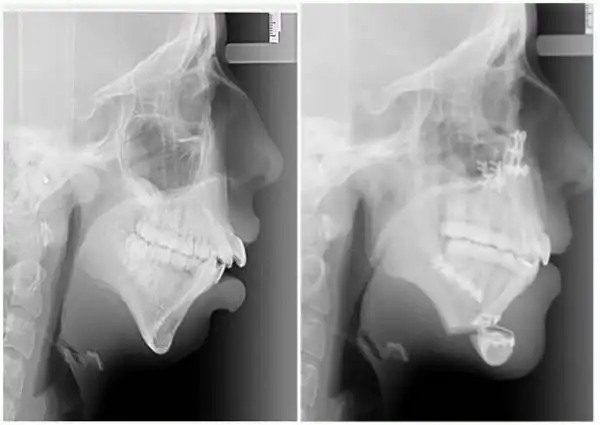

Девушка по имени Элли Джонс (Ellie Jones) родилась с врожденным состоянием лица, которое отразилось на том, что в возрасте 8 лет челюсть Элли просто перестала расти. В результате этого кости нижней части лица девушки перестали развиваться должным образом и были меньше нормального размера. Этот недуг был обнаружен ортодонтом, который сразу догадался в чём проблема, как только девушка пришла к нему на установку скобок в 14 лет.

В течение следующих 6 лет Элли посещала челюстно-лицевого хирурга Эмму Вулли из госпиталя Глан Клвид, Британия, изменить не только свою челюсть, но и жизнь. Предлагаем вам взглянуть на фантастические результаты, которых им удалось добиться.

Первую операцию по преобразованию челюсти Элли перенесла в 16 лет.

Операция заключалась в вырезании челюсти по горизонтали и вертикали с последующим ещё большим хирургическим вмешательством.